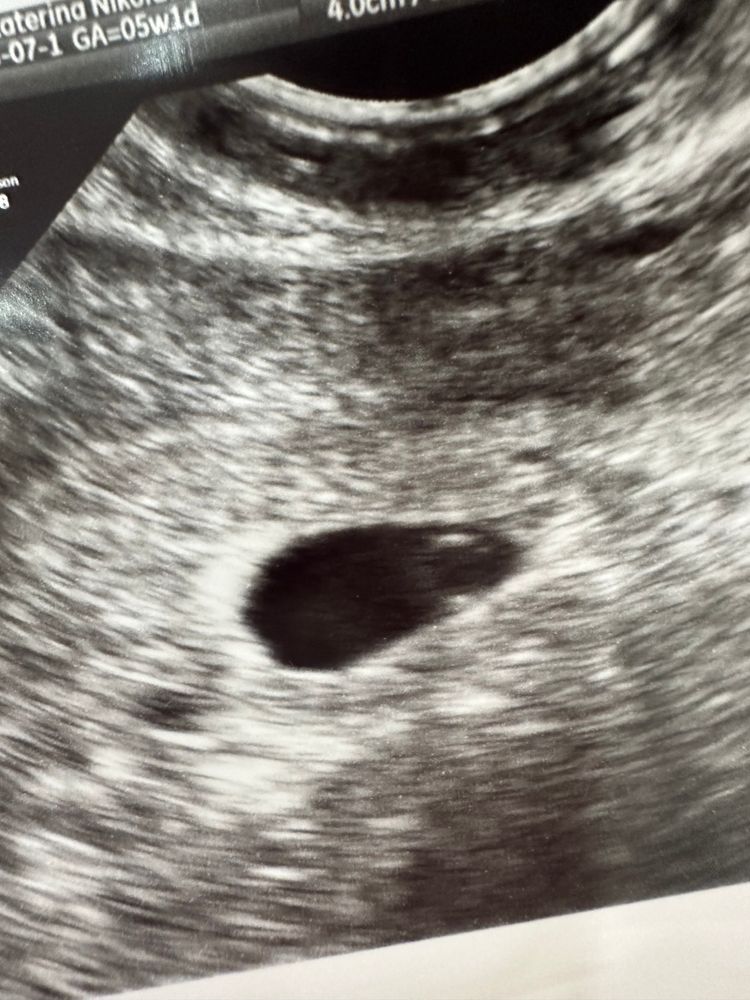

18 дпп, узи ❤️

Всё о нашей беременностиМалышок на базе, увидели ЖМ и КТР ❤️.

Теперь на 24 ДПП надеемся увидеть сердечко.